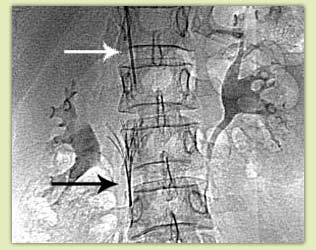

Рис.6 Рентгенограмма: кава-фильтр (черная

стрелка) установлен в нижней полой вене

через доставляющую систему (белая стрелка)

Установка кава-фильтра производится через катетер диаметром 2-3 мм, введенный через бедренную вену (укол производится в паховой складке), подключичную вену (укол производится под ключицей) или яремную вену (укол производится на шее). Это практически безболезненная процедура, не оказывающая влияния на качество жизни и не требующая последующего применения каких-либо препаратов

(рис. 6). После установки фильтра могут возникнуть боли в пояснице, напоминающие радикулит, которые лечатся аналогично радикулиту, и, как правило бесследно проходят в течение недели. Приступ болей в пояснице у больных с установленным кава-фильтром может являться признаком отрыва тромба и задержания его фильтром. В этом случае необходимо провести допплеровское исследование нижней полой вены и/или контрастное исследование вен.